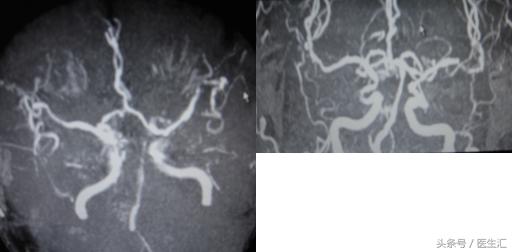

DSA:BA与LVA交界处斑块影,BA远端不显影,从VA缓慢注入rtPA35mg,复查BA、PCA再通(见图20)。但NIHSS评分改善不显著。